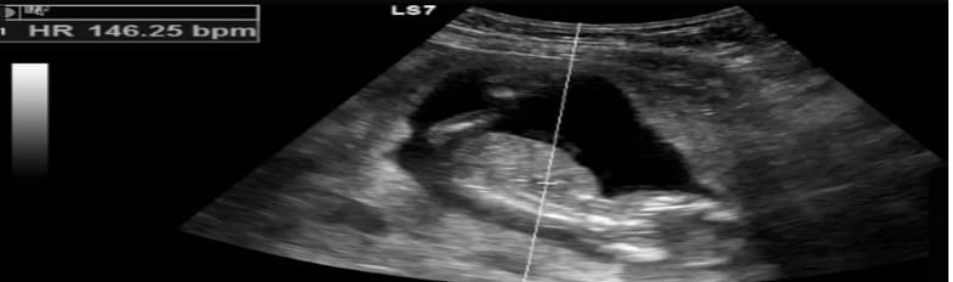

Case Description: A 31-year-old pregnant patient at her 12 weeks of  gestation was admitted. We reported her history of headache, vomiting and acute loss of consciousness. Presenting with GCS 3/15 on arrival, unequal, non-reactive pupils on physical examination, she was intubated because of low GCS and impaired respiratory function. Imaging scans revealed a thalamic hematoma on the left side of large size as well as extensive brain edema and signs of herniation of the brain. Emergency decompressive craniectomy was carried out in a bid to lower intracranial pressure. Because of the patient's pregnancy, an apnea test was not possible as it was a risk to fetal health. The patient also had a craniectomy which made it impossible to use an EEG to determine brain function. A CT angiogram was necessary to rule out vascular causes which was not conducted because there was a high risks of radiation exposure to the fetus.